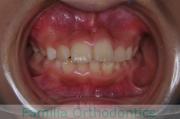

下の前歯が後ろにあるのが気になるとのことで来院されました。非抜歯で行うことも可能でしたが、上下左右から小臼歯抜歯をして治療を行うことをご希望になりました。

マルチブラケット法にて治療を行い、約3年、40回の通院が要でした。

かみ合わせが深い(上の前歯で下の前歯が覆われてしまう)ので、保定をしっかりしないと、また深くなってきてしまいやすいです。